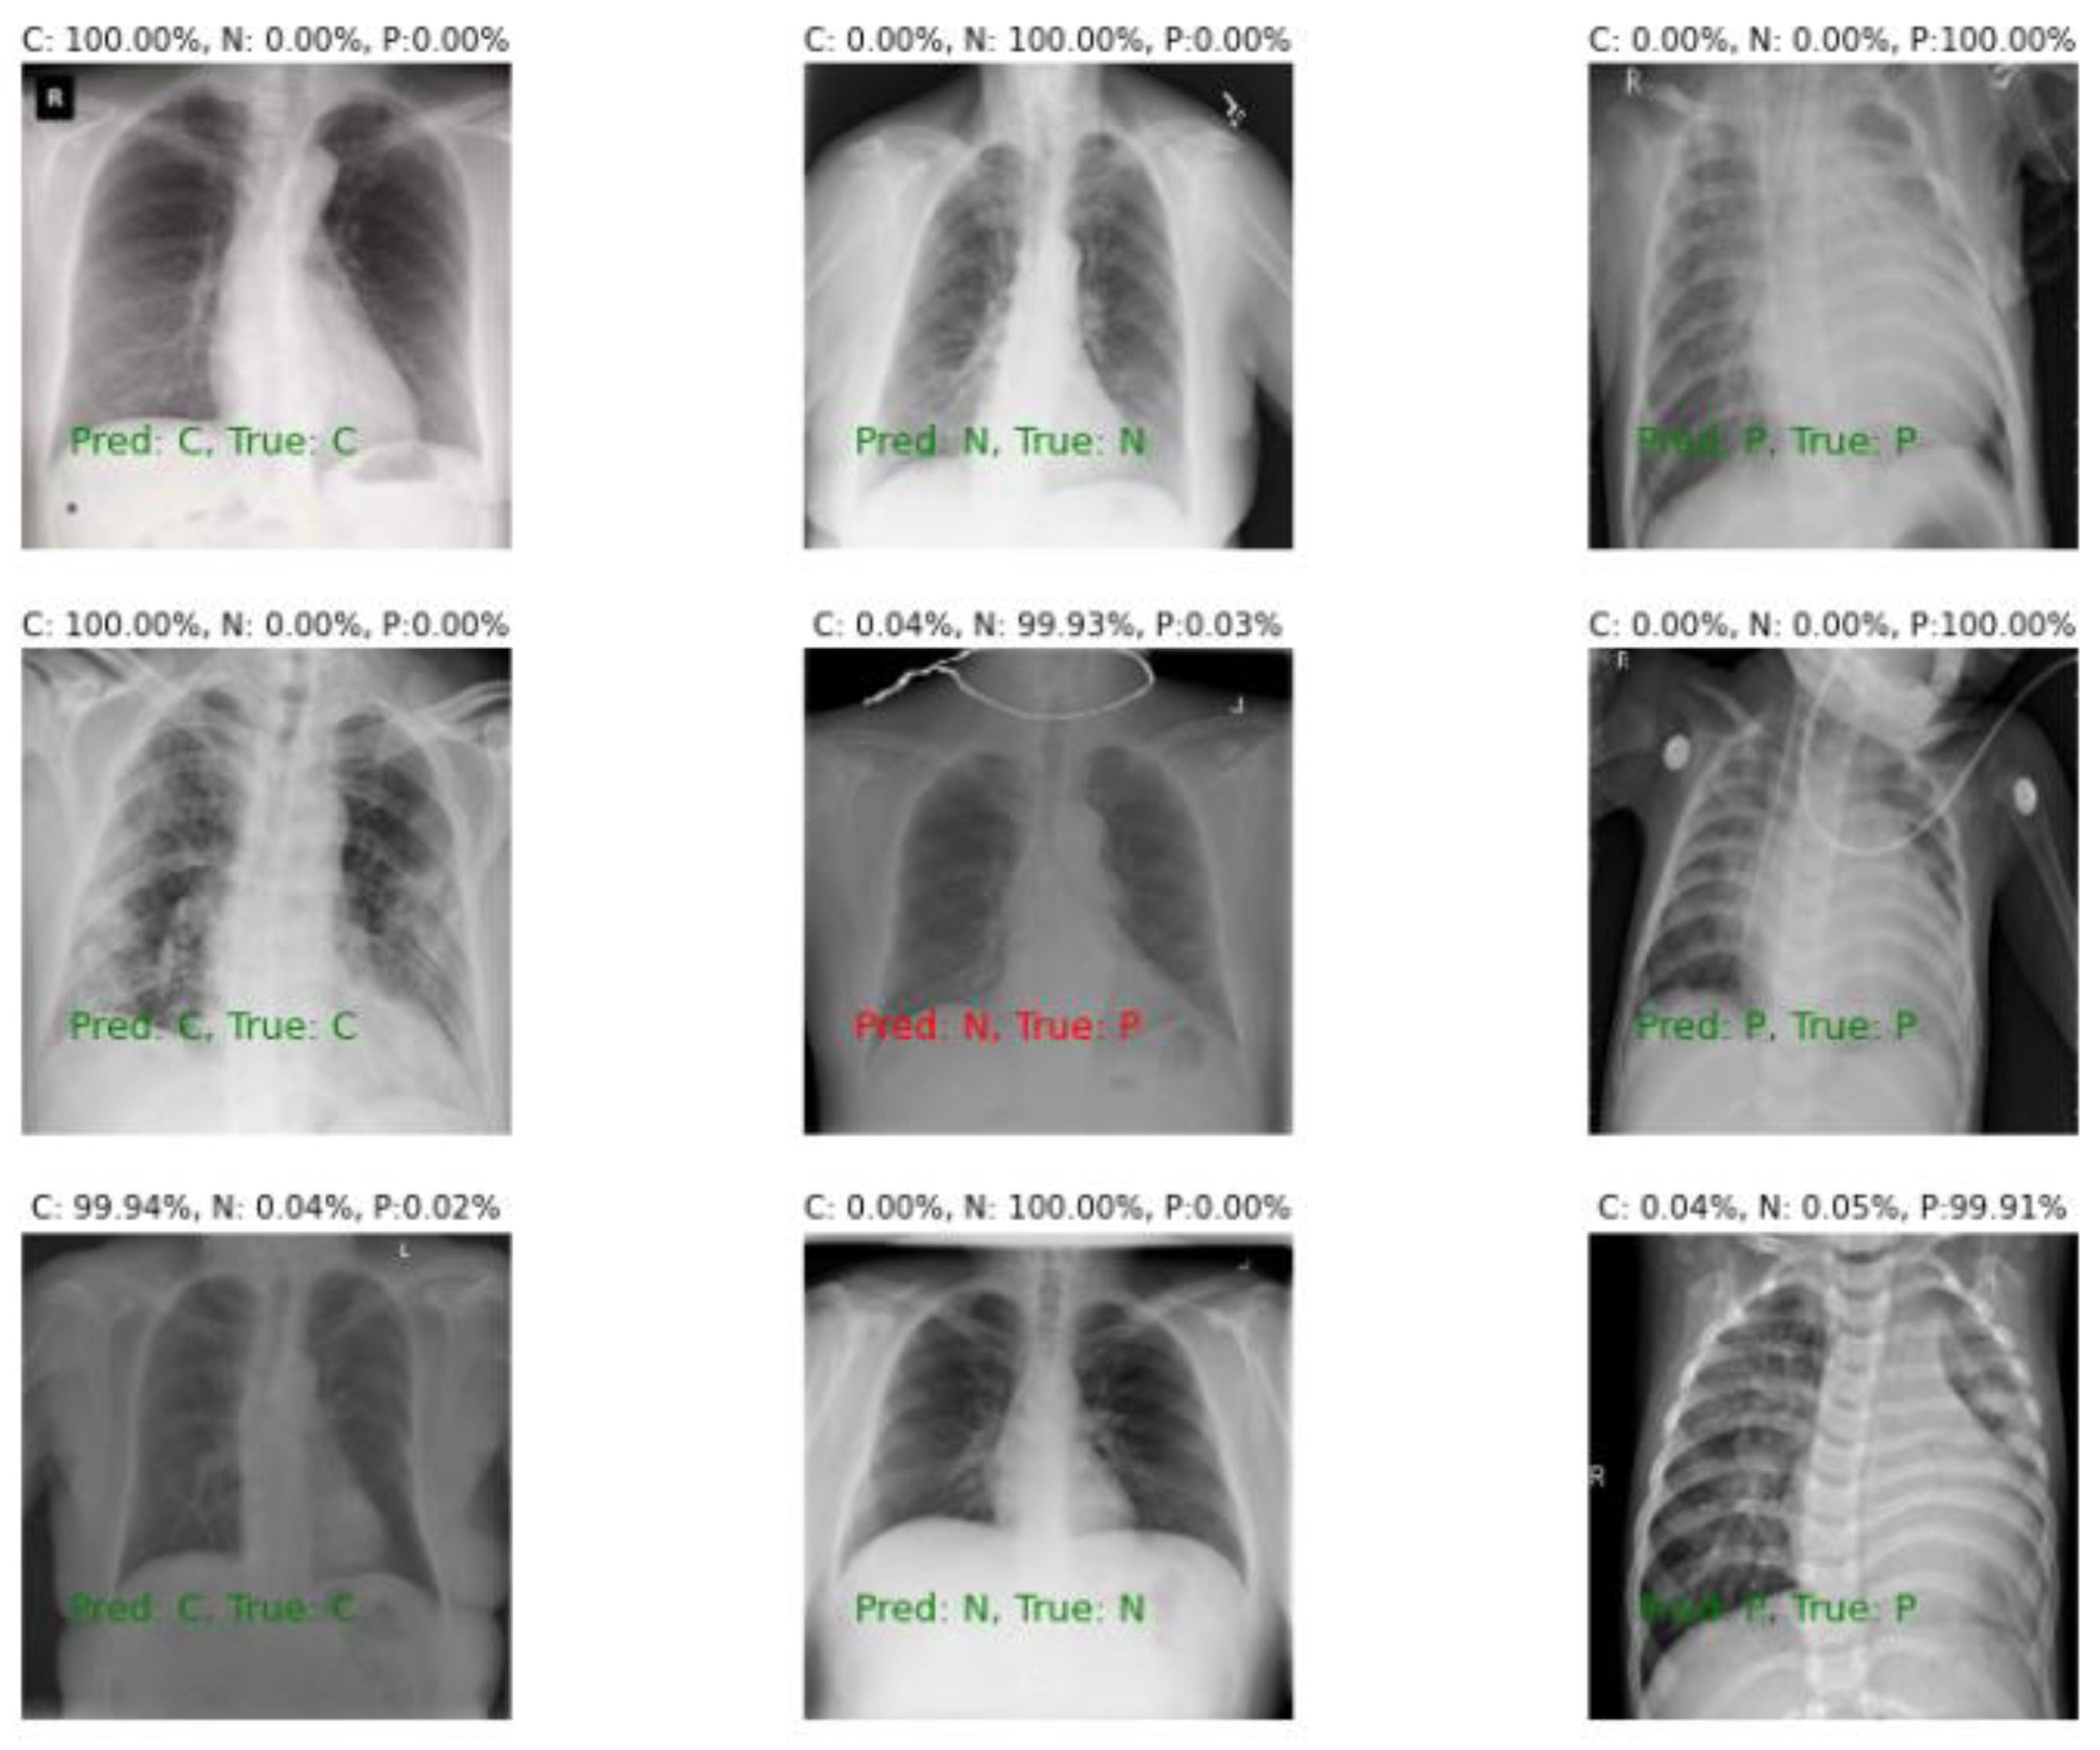

5. Visualization